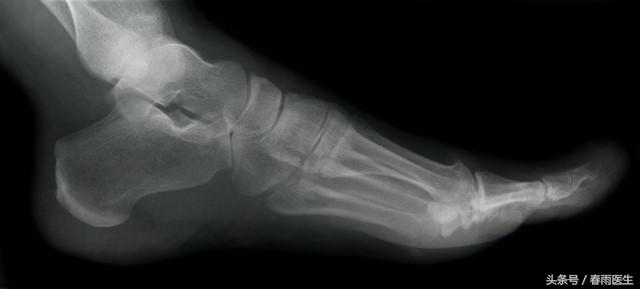

踝关节出现了肿胀、畸形、明显疼痛、并无法再负重行走,甚至在移动后出血,有可能是骨折了。

如果怀疑有骨折的情况,需要及时就医,进行X光检查。再次强调,在医生处理前不要强行移动,或者强行伸展骨折部位,这样可能会让骨折加重。如果骨折部分变形,且身体其他部位的皮肤变凉,苍白无血色,甚至范蓝,可以轻轻地将肢体纵向拉伸。骨折也分不同的情况: